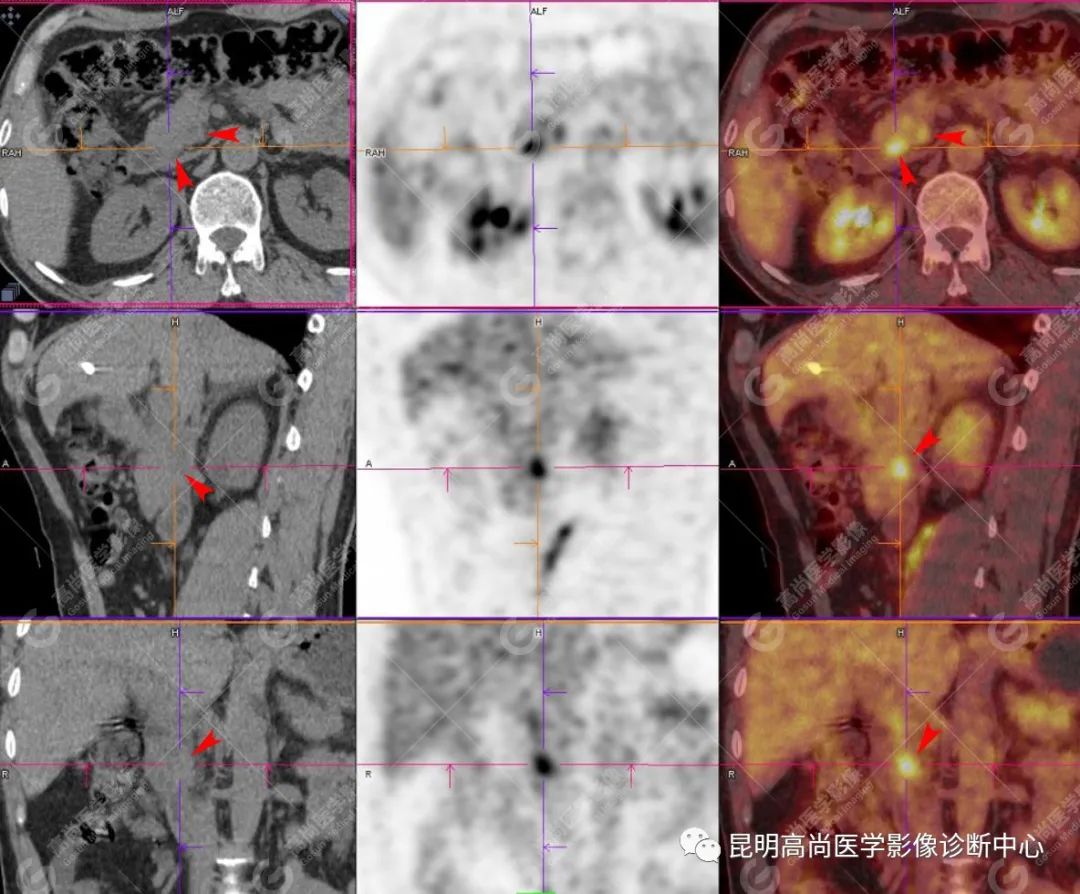

检查图像

影像诊断

十二指肠壶腹区等密度结节影伴糖代谢持续增高,多考虑恶性病变(壶腹癌),继发主胰管扩张及慢性胰腺炎表现;腹膜后多发淋巴结显示,糖代谢不同程度增高,不除外转移。

(4)18F-FDG PET/CT

在诊断胰腺癌方面具有较高的敏感性,其敏感性可达 85%~90%,特异性可达 55.6%~94%;尤其在鉴别良恶性的囊性肿瘤时,其准确率可达到 94%~95%;PET/CT 是胰腺癌的主要检查手段,它比常规 CT 和 MRI 更具优势,可早期发现远处转移灶;同时可以作为一个独立的、用于预测胰腺癌生存和无进展生存的独立的指标,即 SUV,代谢肿瘤体积,即 MTV。